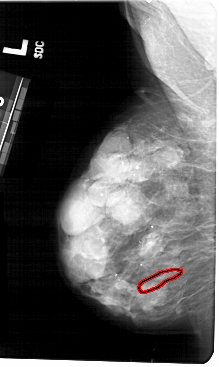

A_1484_1.LEFT_CC

LEFT_CC LINES 5101 PIXELS_PER_LINE 2851 BITS_PER_PIXEL 12 RESOLUTION 43.5 OVERLAY

FILE: A_1484_1.LEFT_CC.OVERLAY

TOTAL_ABNORMALITIES 1

ABNORMALITY 1

LESION_TYPE CALCIFICATION TYPE PLEOMORPHIC DISTRIBUTION LINEAR

ASSESSMENT 4

SUBTLETY 1

PATHOLOGY BENIGN

TOTAL_OUTLINES 1

BOUNDARY